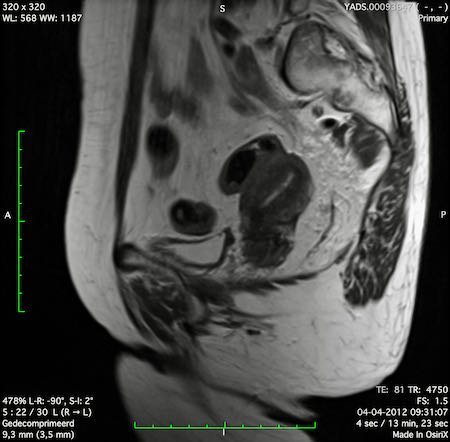

Hình ảnh

Các hình ảnh được cung cấp cho thấy ung thư biểu mô tế bào nhẫn với tình trạng dày lan tỏa thành trực tràng, hình ảnh bia bắn điển hình, và sự xâm lấn mỡ mạc treo trực tràng.